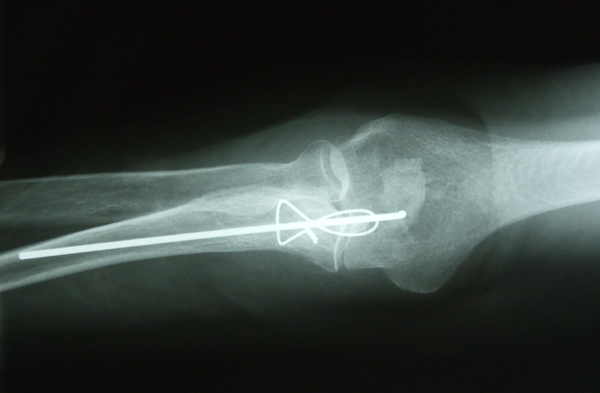

AVC amplio de territorio de A. cerebral media